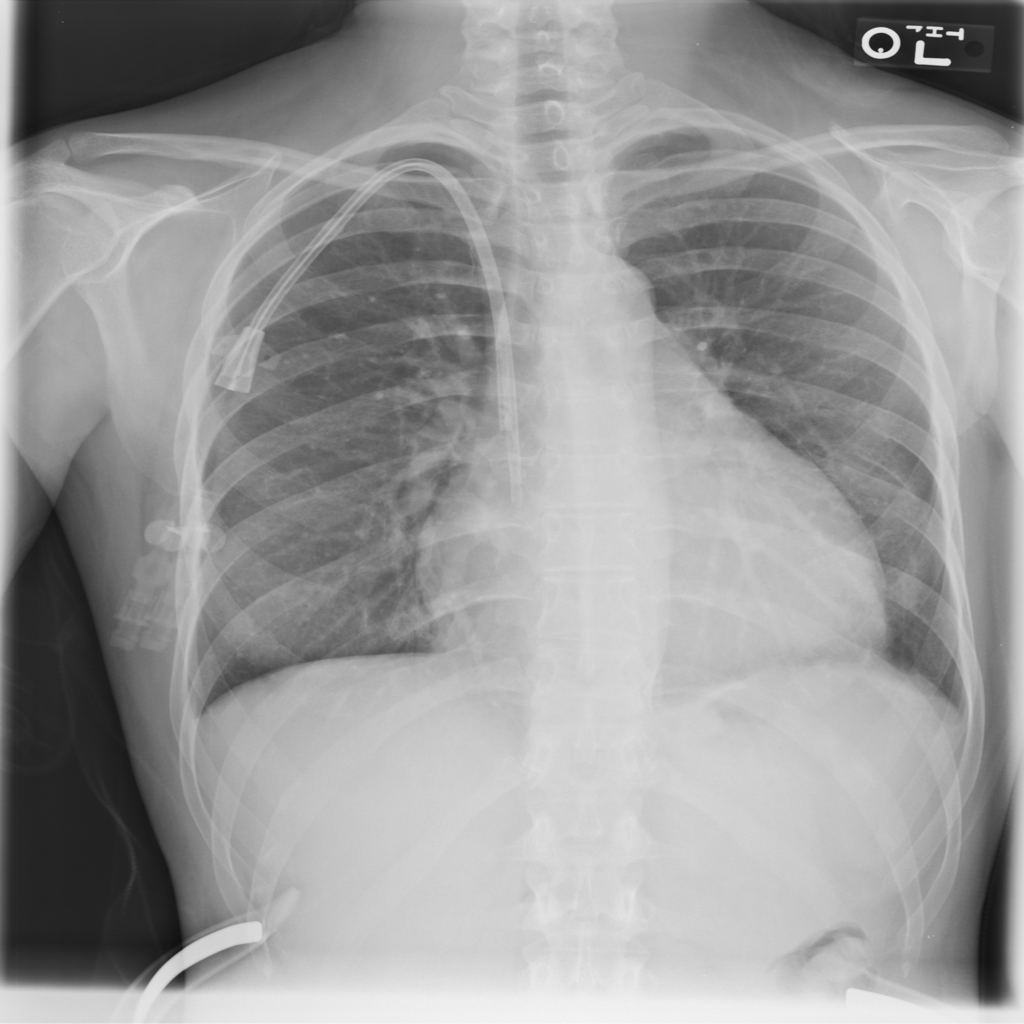

PAT-3384 · IMG-000Cardiomegaly

PAT-3384 · IMG-000

AP